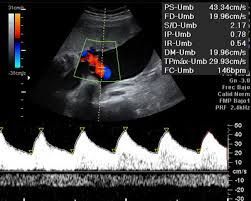

Este ultrasonido funciona con un transductor especial que le permite al equipo realizar tres cortes sonográficos en blanco y negro. Gracias a que trae una computadora integrada, el equipo de ultrasonido nos regala una imagen tridimensional en color en alta calidad.